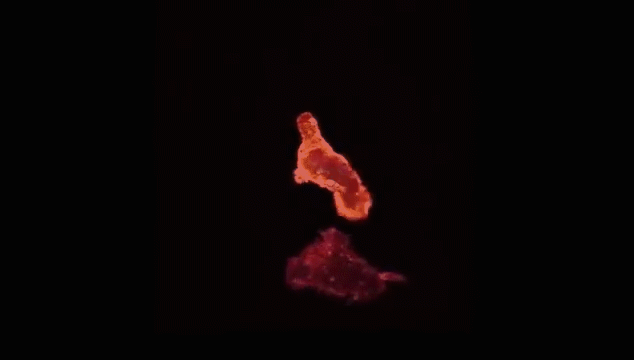

查明之后,T细胞(红)连接癌细胞(蓝),打破癌细胞外壁,向其表面引入毒性蛋白。

一旦细胞毒素(红)进入,癌细胞会逐渐衰弱、死亡。而T细胞(绿)继续在人体内巡逻,寻找下一个目标。